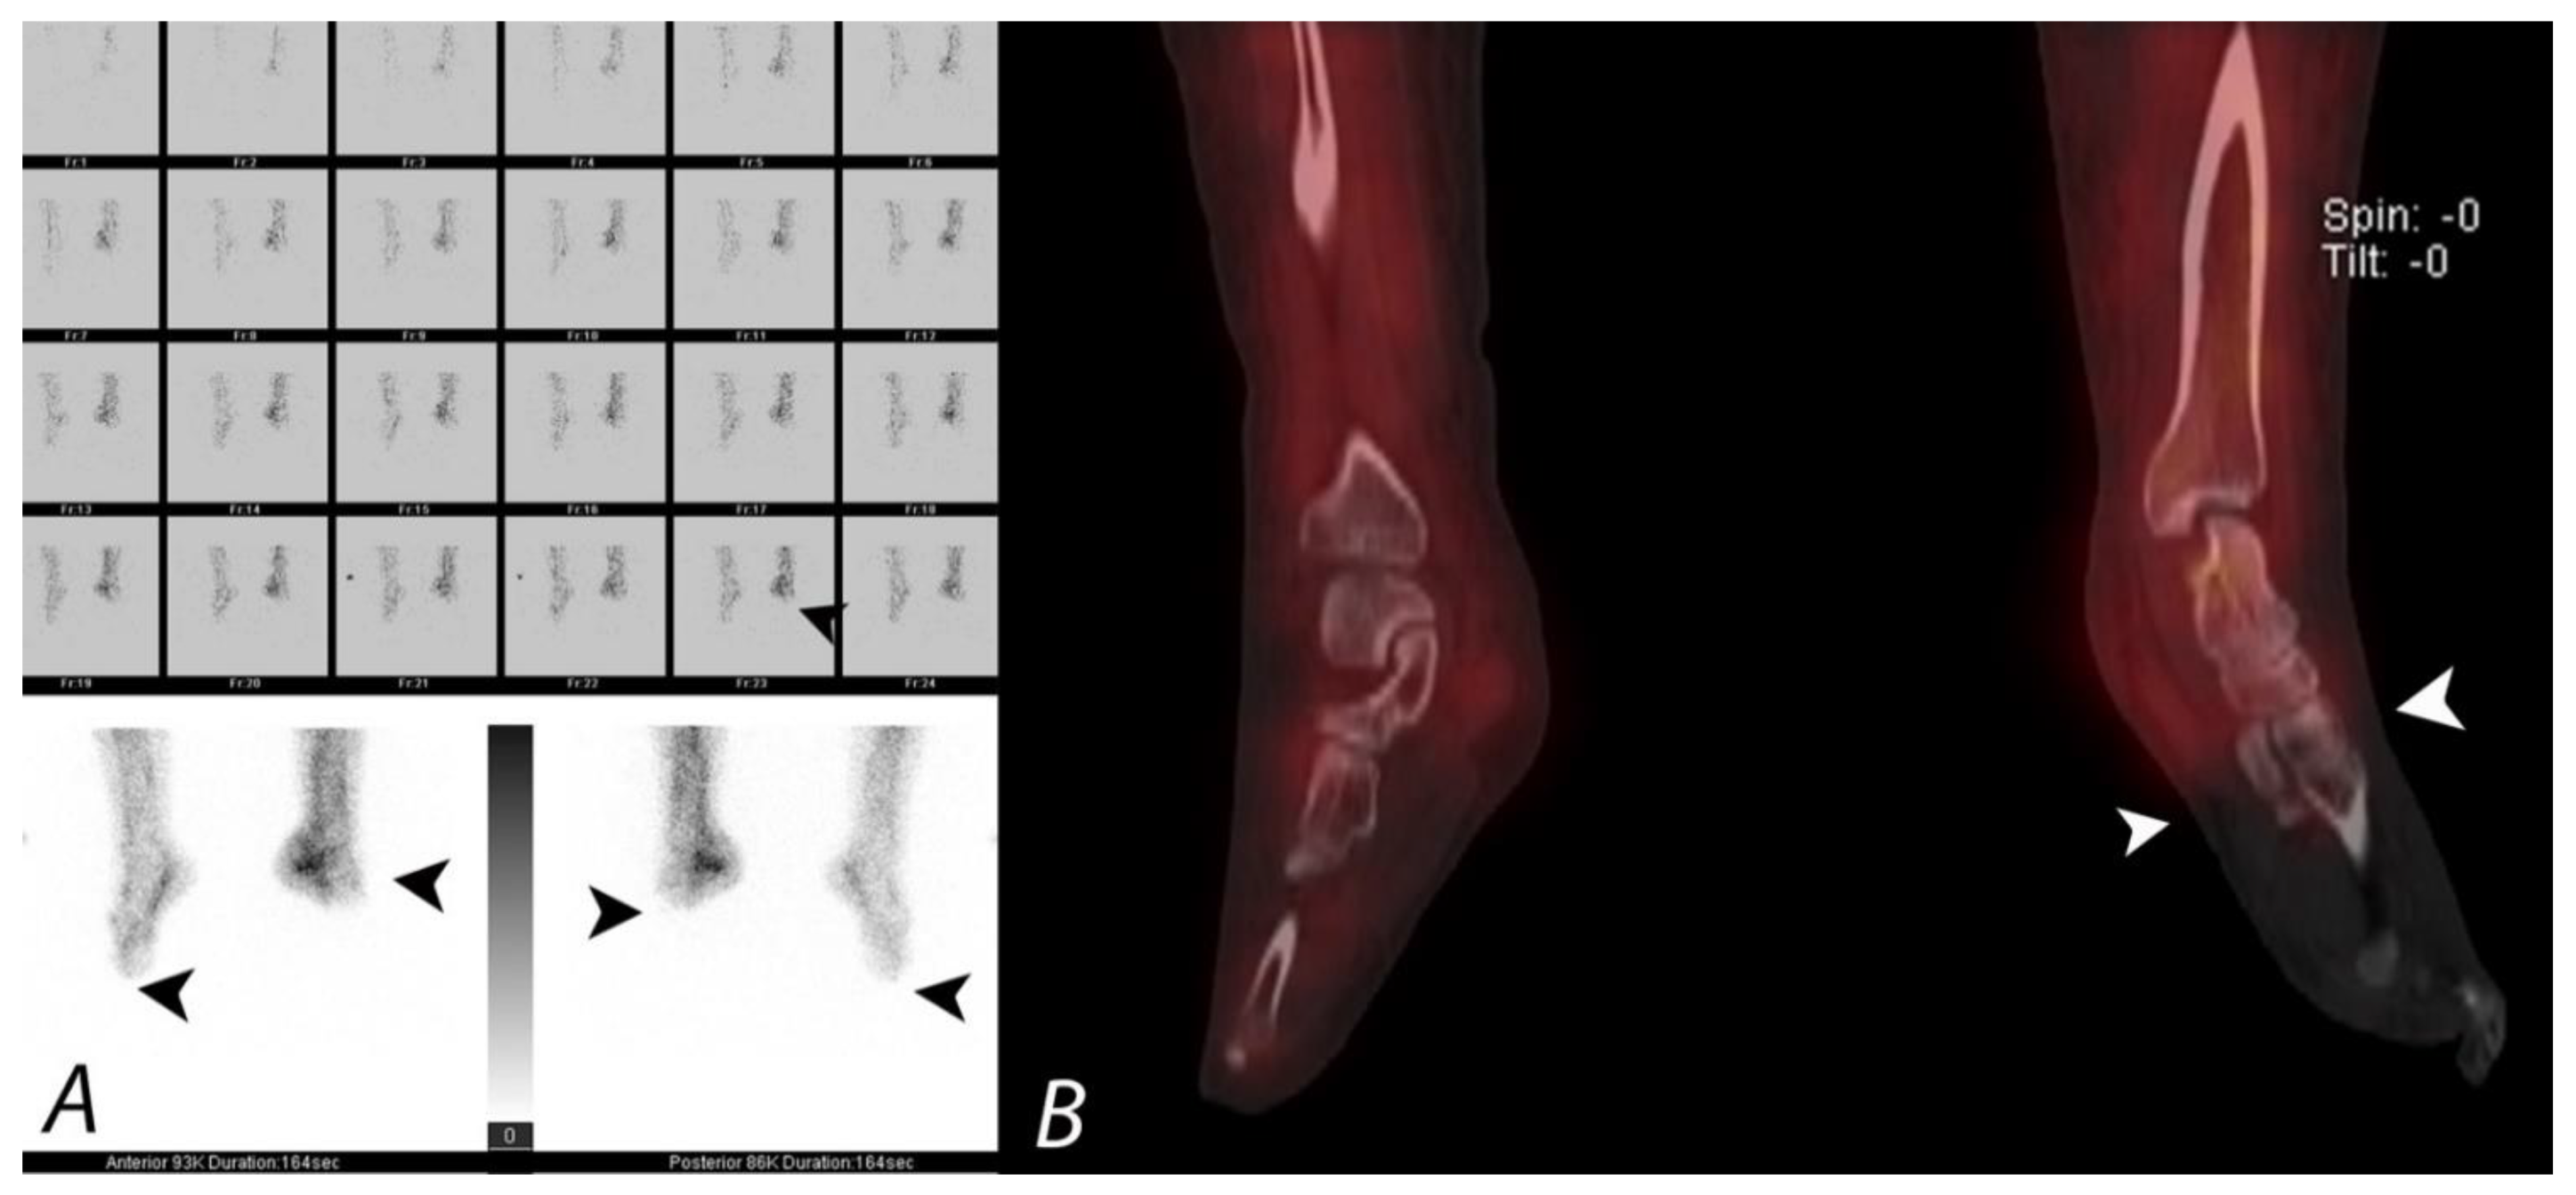

Figure 17.

Patient presenting with severe cold injury (frostbite) to bilateral feet underwent three phase bone to evaluate for the extent of devascularization as a part of presurgical evaluation. Blood flow images and blood pool images (A) demonstrate absent perfusion and pool activity involving the fore foot and mid foot on the left side and involving the forefoot on the right side. Coronal SPECT/CT (B) confirms the findings with accurate delineation and demarcation of viable and non-viable tissue. Patient underwent bilateral below knee amputation.

The patterns of uptake on each phase of the bone scan correlates well with the clinical management, with minor injury demonstrating hyper-perfusion and normal soft tissue and delayed uptake, requiring no surgical intervention on any part of the spectrum of severe injury, with deep gangrene and bone infarction requiring amputation and bone scan demonstrating absent uptake on all three phases [121].